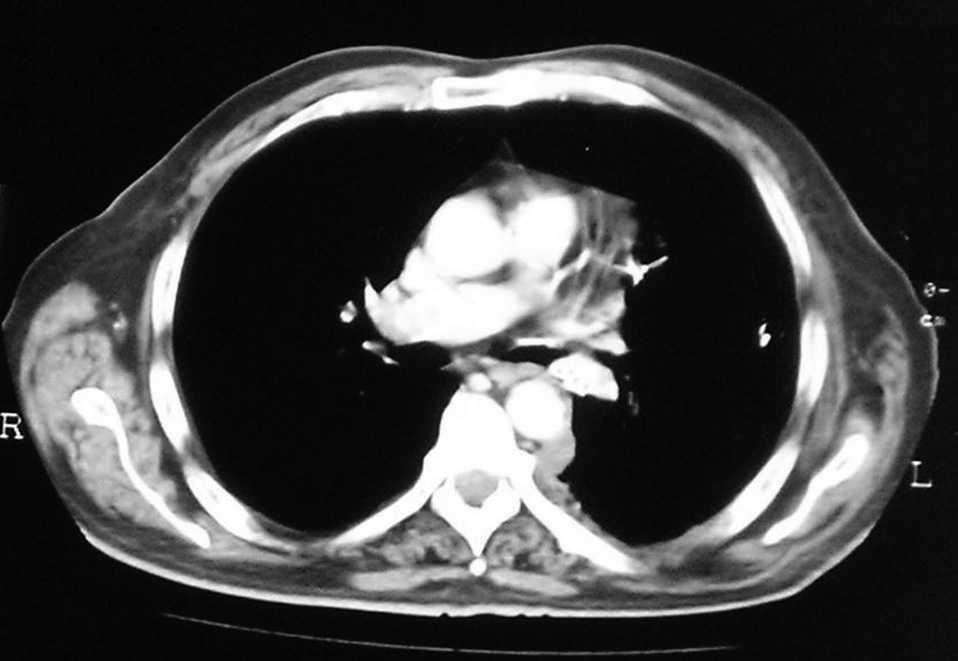

Paciente de 66 años, fumador de 40 paquetes/año, con antecedentes de arteriopatía aterosclerótica de los sectores femoropoplíteos y carotídeos bilaterales, tratada médicamente, que ingresó para estudio de pérdida de la visión de los colores, tras faquectomía bilateral sin complicaciones. Su oftalmólogo indicó que se trataba de un síndrome paraneoplásico y recomendó una evaluación para descartar un posible tumor. La exploración física mostró un Karnofsky del 80%, sin evidencia clínica de enfermedad. La colonoscopia y la gastroscopia descartaron la presencia de enfermedad. La radiografía posteroanterior de tórax reveló sólo un hilio izquierdo ensanchado (fig. 1). La tomografía computarizada torácica mostró una lesión de aspecto tumoral de 2,5 cm, localizada en el segmento posterior del lóbulo inferior izquierdo (fig. 2), que no captó contraste, con discretas atelectasias subsegmentarias en esa zona. También reveló cambios enfisematosos en los lóbulos superiores. En el mediastino no se identificaron adenopatías de tamaño patológico. El hígado y las suprarrenales no mostraron lesiones. La broncoscopia evidenció una lesión endobronquial en el segmento posterior del lóbulo inferior izquierdo, que estenosaba totalmente la luz bronquial. La citología del broncoaspirado fue positiva para carcinoma, y la biopsia resultó positiva para carcinoma escamoso no queratinizante. El estudio funcional respiratorio estuvo dentro del rango de la normalidad, con un índice volumen espiratorio forzado en el primer segundo/capacidad vital forzada (2,58/3,54) sobre el 80% del teórico. La gasometría arterial fue normal. La gammagrafía ósea no reveló imágenes compatibles con metástasis.

Fig. 2. Tomografía computarizada de tórax que objetiva una estenosis por tumoración en el segmento VI del bronquio.